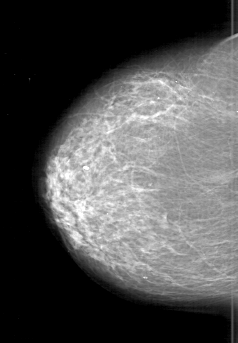

D_4198_1.LEFT_CC

RIGHT_CC LINES 6166 PIXELS_PER_LINE 4276 BITS_PER_PIXEL 12 RESOLUTION 43.5 NON_OVERLAY